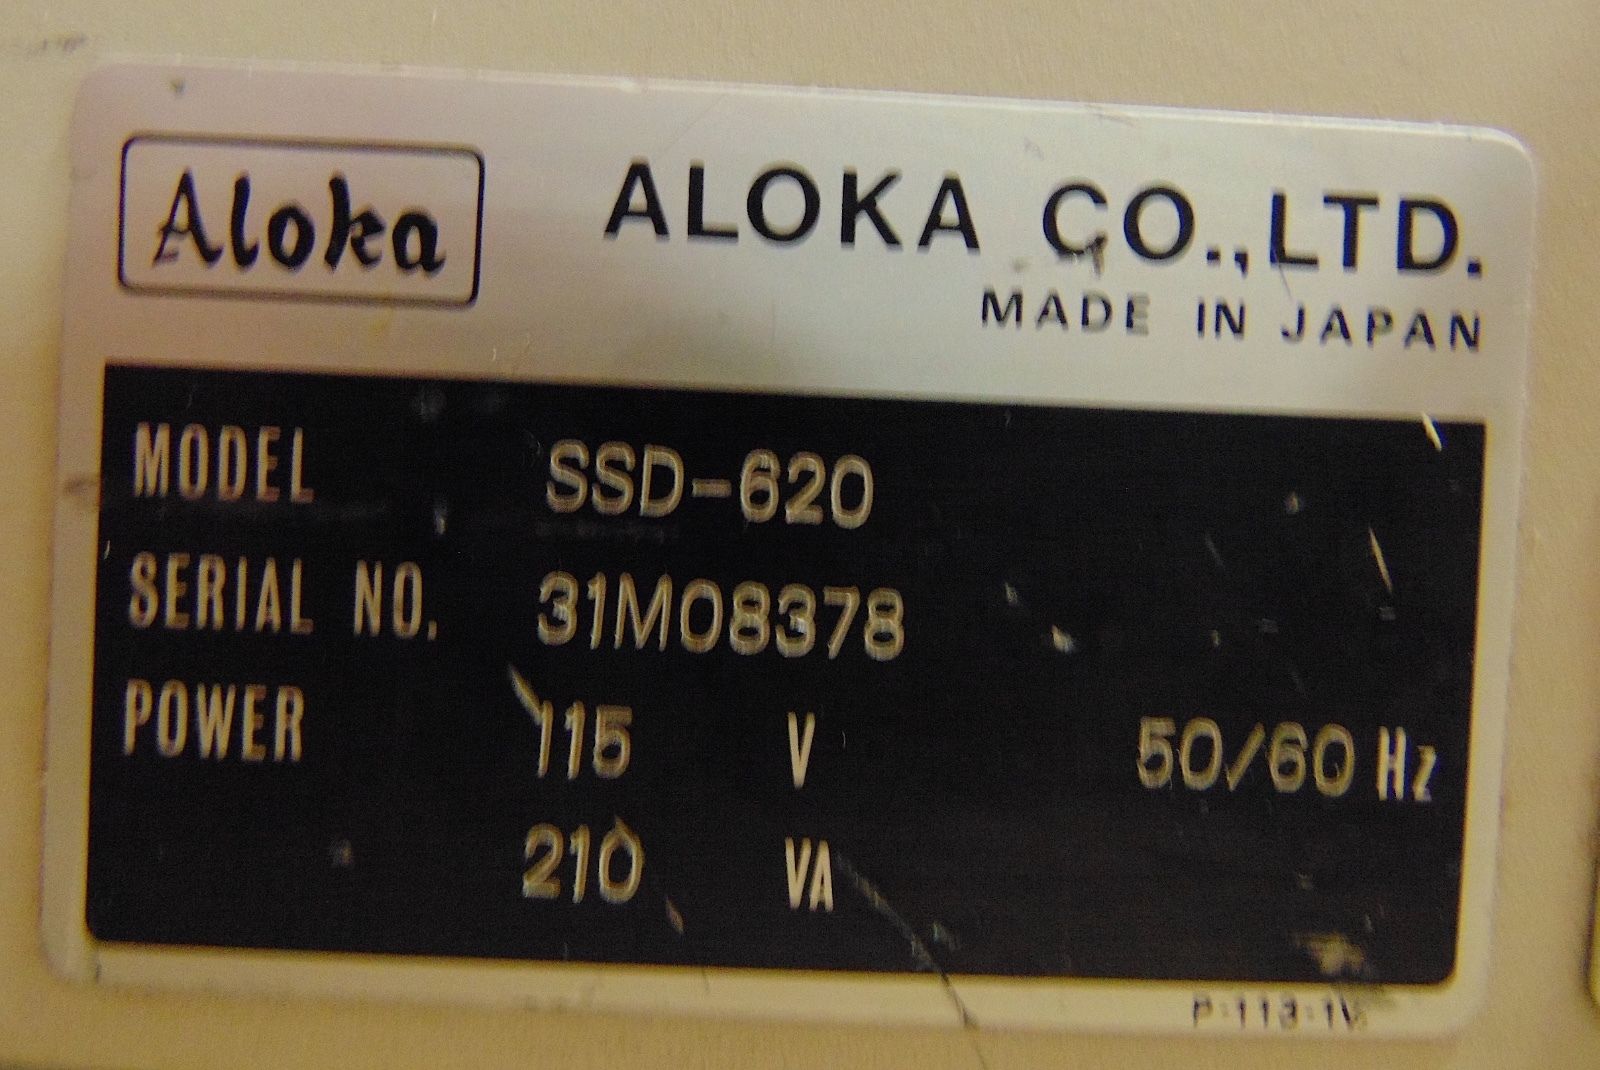

Brand: Aloka

MPN: 31M08378

Model: SSD-620

Country/Region of Manufacture: Japan